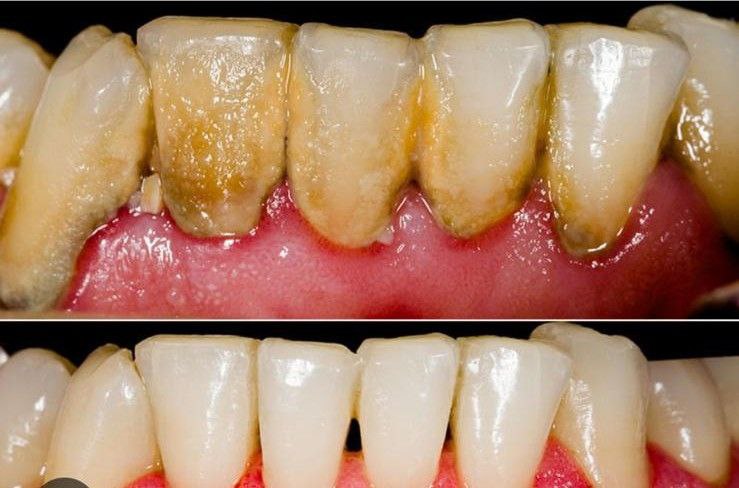

soins parodontaux

Soins des gencives et prévention du déchaussement dentaire.

Pour une bouche saine et un sourire durable.